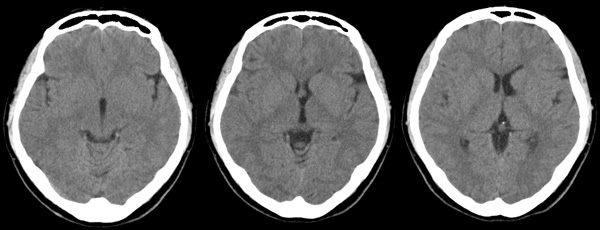

f24y打架后头疼3天,5mm薄扫

左侧侧脑室体三角形扩大,其外上方一小凹陷,左顶部脑沟稍宽,考虑脑裂畸形。

ct所见:左侧顶叶近侧脑室体部处示斑片状低密度灶,同侧脑室扩大,脑沟及脑裂增宽。颅骨结构完整。

诊断:符合脑软化灶,可以结合以往病史进行临床分析,如新生儿时的脑缺氧、血管畸形、后天性的各种原因引起的缺血缺氧、陈旧性的外伤等。由于部分容积效应的原因,左侧脑实质的低密度灶看似与侧脑室相通,必要时可以作mr检查以鉴别有无脑穿通畸形的可能。该病灶与此次外伤无关。

左侧侧基底节区软化灶,左侧脑室前角、体部被牵拉扩大,仔细观察左侧侧裂池及部分脑沟增宽,提示左侧颞叶有轻度萎缩,上述改变为陈旧性病变,与此次头外伤无关,其病因分析有以下可能:缺氧、脑炎、外伤等。